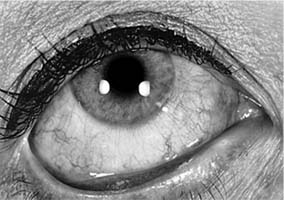

Rheumatoid factor, an IgM autoantibody directed against the patient's own IgG, may play a major role in the pathogenesis of rheumatoid arthritis. The union of IgM antibody with IgG is followed by fixation of complement at the tissue site and the attraction of leukocytes and platelets to this area. An occlusive vasculitis, resulting from this chain of events, is thought to be the cause of rheumatoid nodule formation in the sclera as well as elsewhere in the body. The occlusion of vessels supplying nutrients to the sclera is thought to be responsible for the "melting away" of the scleral collagen that is so characteristic of rheumatoid arthritis (Figure 16-6).

Figure 16-6

Figure 16-6: Scleral thinning in a patient with rheumatoid arthritis. Note dark color of the underlying uvea.